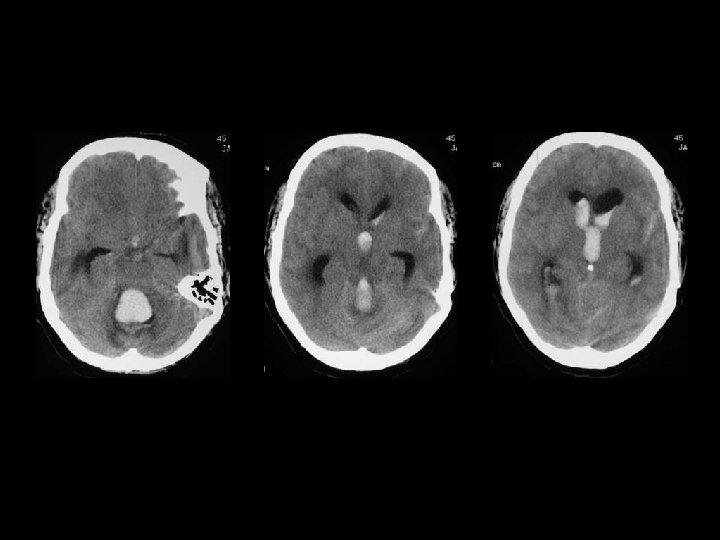

Perdarahan Intraventricular n Paling sering akibat ruptur pembuluh darah subependymal n Dapat timbul akibat refluks dari SAH atau perluasan dari perdarahan intraserebral n Lihat adanya blood-cerebrospinal fluid level di occipital horns

Intraparenchymal hematoma n Kumpulan darah fokal yang tersering timbul dari shear-strain injury pada pembuluh darah intraparenkim n Umumnya berlokasi pd frontotemporal white matter atau basal ganglia n Hematoma di dalam parenkim otak yang normal n DDx: DAI, hemorrhagic contusion